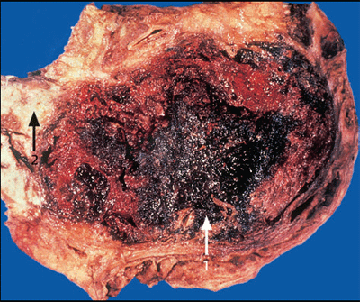

Особое место в патогенезе опосредованных повреждений ЖКТ следует отвести роли пролон-гированной искусственной вентиляции легких (ИВЛ), поскольку выявлено и доказано снижение параметров спланхического кровообращения в целом и локальной гипоперфузии пищеварительной системы в качестве негативного влияния ИВЛ (особенно с положительным давлением конца вдоха - PEEP) на функциональное состояние ЖКТ. Проведение ИВЛ с положительным давлением конца вдоха (PEEP) приводит к повышению внутригрудного давления, снижению венозного возврата за счет уменьшения градиента между средним давлением в венозной системе и давлением в правом предсердии. Уменьшение преднаг- рузки вызывает снижение сердечного выброса и гипотонию, которая более выражена у пациентов с фоновой гиповолемией, а также у лиц со сниженной способностью венозного русла к вазоконстрикции (например, при назначении во время ИВЛ опиатов). В ряде исследований было доказано, что применение PEEP способствует снижению кровотока не только в кишечнике, но и в поджелудочной железе и желудке, оказывает негативное влияние на показатели портального и печеночного артериального кровотока, а также на уровень оксигенации крови в печеночных венах (диагностический показатель адекватности снабжения печени кислородом). В последние годы появились данные об увеличении внутрибрюшного давления во время ИВЛ с PEEP, существенно влияющего на снижение спланхической гемодинамики. Этот эффект особенно заметен у больных с гипоксемией, гипотензией, а также при любых других патологических состояниях, ухудшающих снабжение тканей кислородом [10,24,25,42,45,51,63,66]. Снижение показателей системной и локальной гемодинамики в условиях стресса и повышенного сосудистого сопротивления приводят к ишемии слизистой оболочки желудка и кишечника и повреждению ее целостности (образование эрозий, язв) (рис. 1), а также замедлению скорости опорожнения желудка и снижению перистальтической активности кишечника [50]. Гипоксия органов желудочно-кишечного тракта возникает при их неадекватном снабжении кислородом и другими необходимыми веществами. В различных слоях органов желудочно-кишечного тракта чувстви-тельность тканей к ишемии неодинакова. Снижение кровотока наблюдается при так называемой «генерализованной ишемии без окклюзии» (циркуляторный шок, сердечная недостаточность) и при окклюзии сосудов брыжейки (атеросклероз, эмболии, тромбоз)[6,16,34,72].

Рис. 1. Повреждение целостности слизистой обо-лочки желудка и кишечника